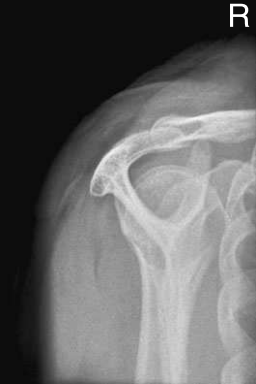

영상평가

- arcromion(견봉)의 전체적인 모습이 잘 보여야 한다.

- scauplar(견갑골)은 Y자 모양이 나와야 한다.

- supraspinauts(극상근)이 차지하는 공간이 잘 나와야 한다.

- AC joint(견쇄관절), scapular가 잘 보여야 한다.